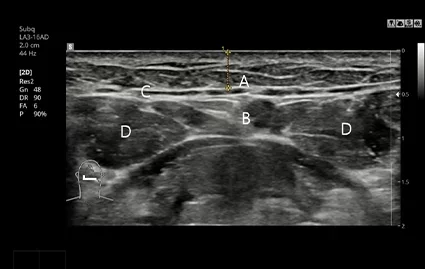

手術前 CTおよび超音波撮影

CT撮影および超音波検診で唾液腺の位置と大きさを精密に分析し、必要に応じて繊細なオーダーメイド唾液腺除去手術を進行